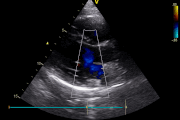

Echocardiography Heart Imaging Blood Flow Analysis Valve Assessment

Echocardiography is a diagnostic tool that uses ultrasound waves to create a visual image of the heart. It shows heart muscles, valves, blood flow, and evidence of blockages.

It identifies blockages, valve conditions, blood flow pressure, heart aging, lung condition, and tissue damage.

Includes TTE, TEE, Contrast Echo, 3D, 4D, and Speckle Tracking. Used in cancer care, kidney disease, stroke, and systemic illness.